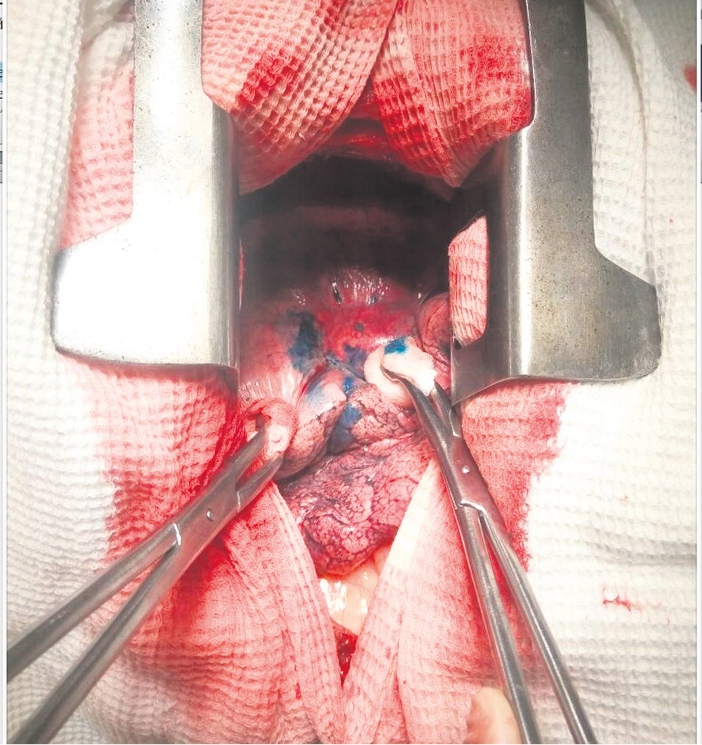

После установки выполнялось эндовидеохирургическое оперативное вмешательство с атипичной резекцией зоны инфильтрата с установленной «якорной меткой» и срочным или плановым гистологическим исследованием инфильтрата, в зависимости от клинической ситуации (рис. 7–9).

Рис. 7. Интраоперационное фото пациентки М., 46 лет. идеоторакоскопическая атипичная резекция (биопсия) нижней доли левого легкого в проекции установленной «якорной метки»

Fig. 7. Intraoperative photo of Patient M, female, 46 years old. Ideothoracoscopic atypical resection (biopsy) of the lower lobe of the left lung in the projection of the installed anchor marker